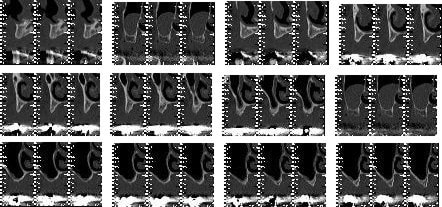

La technique d'élévation sinusienne grace à des ballonnets par voie crestale, technique appelée MIAMBE (Minimally Invasive Antral Membrane Balloon Elevation) est une technique fiable mais destinée à des élevations ponctuelles pour des unitaires. Cette technique n'est pas vraiment indiquée pour la réalisation d'une élévation sinusienne intéressant plusieurs dents (à moins d'avoir un plancher sinusien très plat).

Cela n'est techniquement pas impossible à condition de pratiquer plusieurs puits d'entrée.

Donc pxav, je ne suis pas sûr que le problème vienne du ballonnet mais plutôt de l'indication que tu as fait de cette technique.

tout à fait d'accord avec toi sur le principe, mais (peut etre suis je tombé sur un mauvais lot) le fait d'avoir deux balloons sur trois qui "lache" en quelques secondes (200€ piece) ça m'a sans doute aidé à ne pas apprecier!

je vais quand même faire une autre tentative, il ne faut pas mourir idiot